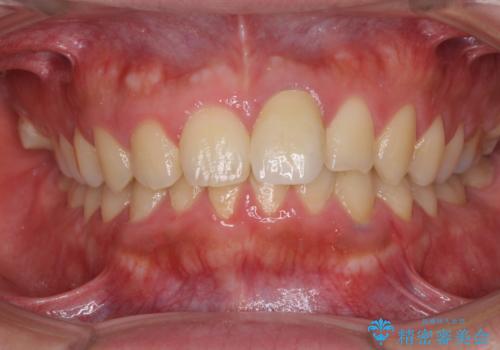

レントゲン写真より、歯の中の神経組織が失活していることが分かったため、根管治療、ファイバーコアによる土台築製を行い、オーダーメイドタイプのオールセラミッククラウンにて補綴することとしました。

人目を気にすることなく話ができるようになり、患者様には大変満足していただきました。